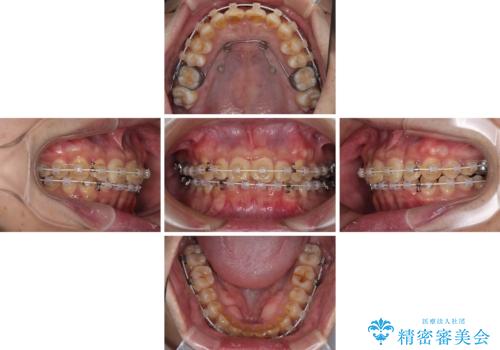

補助装置を用いて、上顎大臼歯を積極的に後方移動させながら、ディープバイトを改善していくこととしました。

強い咬合力に抵抗するため、上下ともに表側のワイヤー装置にて矯正治療を行うこととしました。